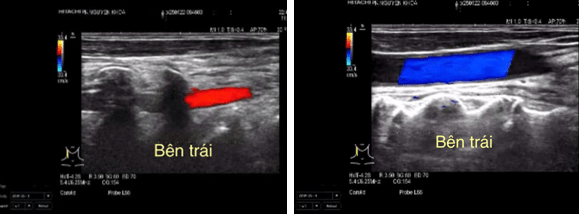

Hình ảnh siêu âm thực hiện tại phòng khám đa khoa Nguyên Khoa

Hình 2. Hình ảnh siêu âm doppler màu cho thấy động mạch đốt sống đảo chiều hoàn toàn so với động mạch cảnh cùng bên.

Hình 3. Hình ảnh siêu âm duplex cho thấy phổ doppler xung của động mạch đốt sống bên trái 1 pha, đảo ngược hoàn toàn thì tâm thu PSV# 49cm/s.